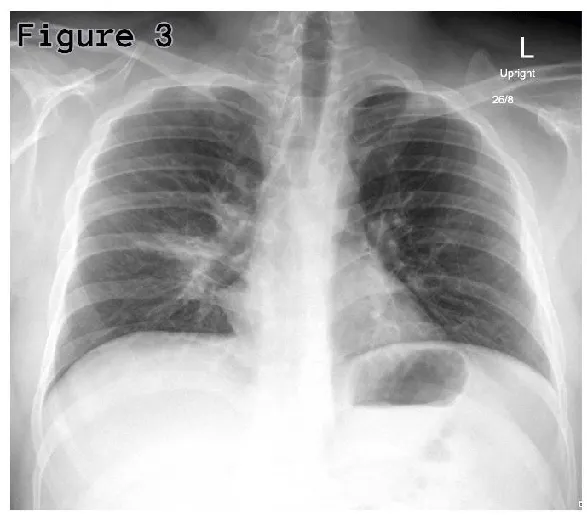

His routine blood investigations showed raised C-reactive protein (135.28 mg/L) and WBCs (12.51×103/mcL); however, his procalcitonin was normal (0.14 ng/mL). His Chest x-ray showed right lower lobe or middle lobe segmental consolidation (Figure 3). Patient’s sputum culture showed growth of normal flora; nevertheless, his serum mycoplasma IgM antibody was found positive, which is consistent with acute mycoplasma infection. His urine analysis showed red blood cell counts (RBCs) of 25-50 per high power field, suggestive of urethral mucositis.

On two weeks follow-up, his chest x-ray showed significant resolution of right side consolidation (Figure 4) and there were no residual lesions in the oral cavity and urethra.